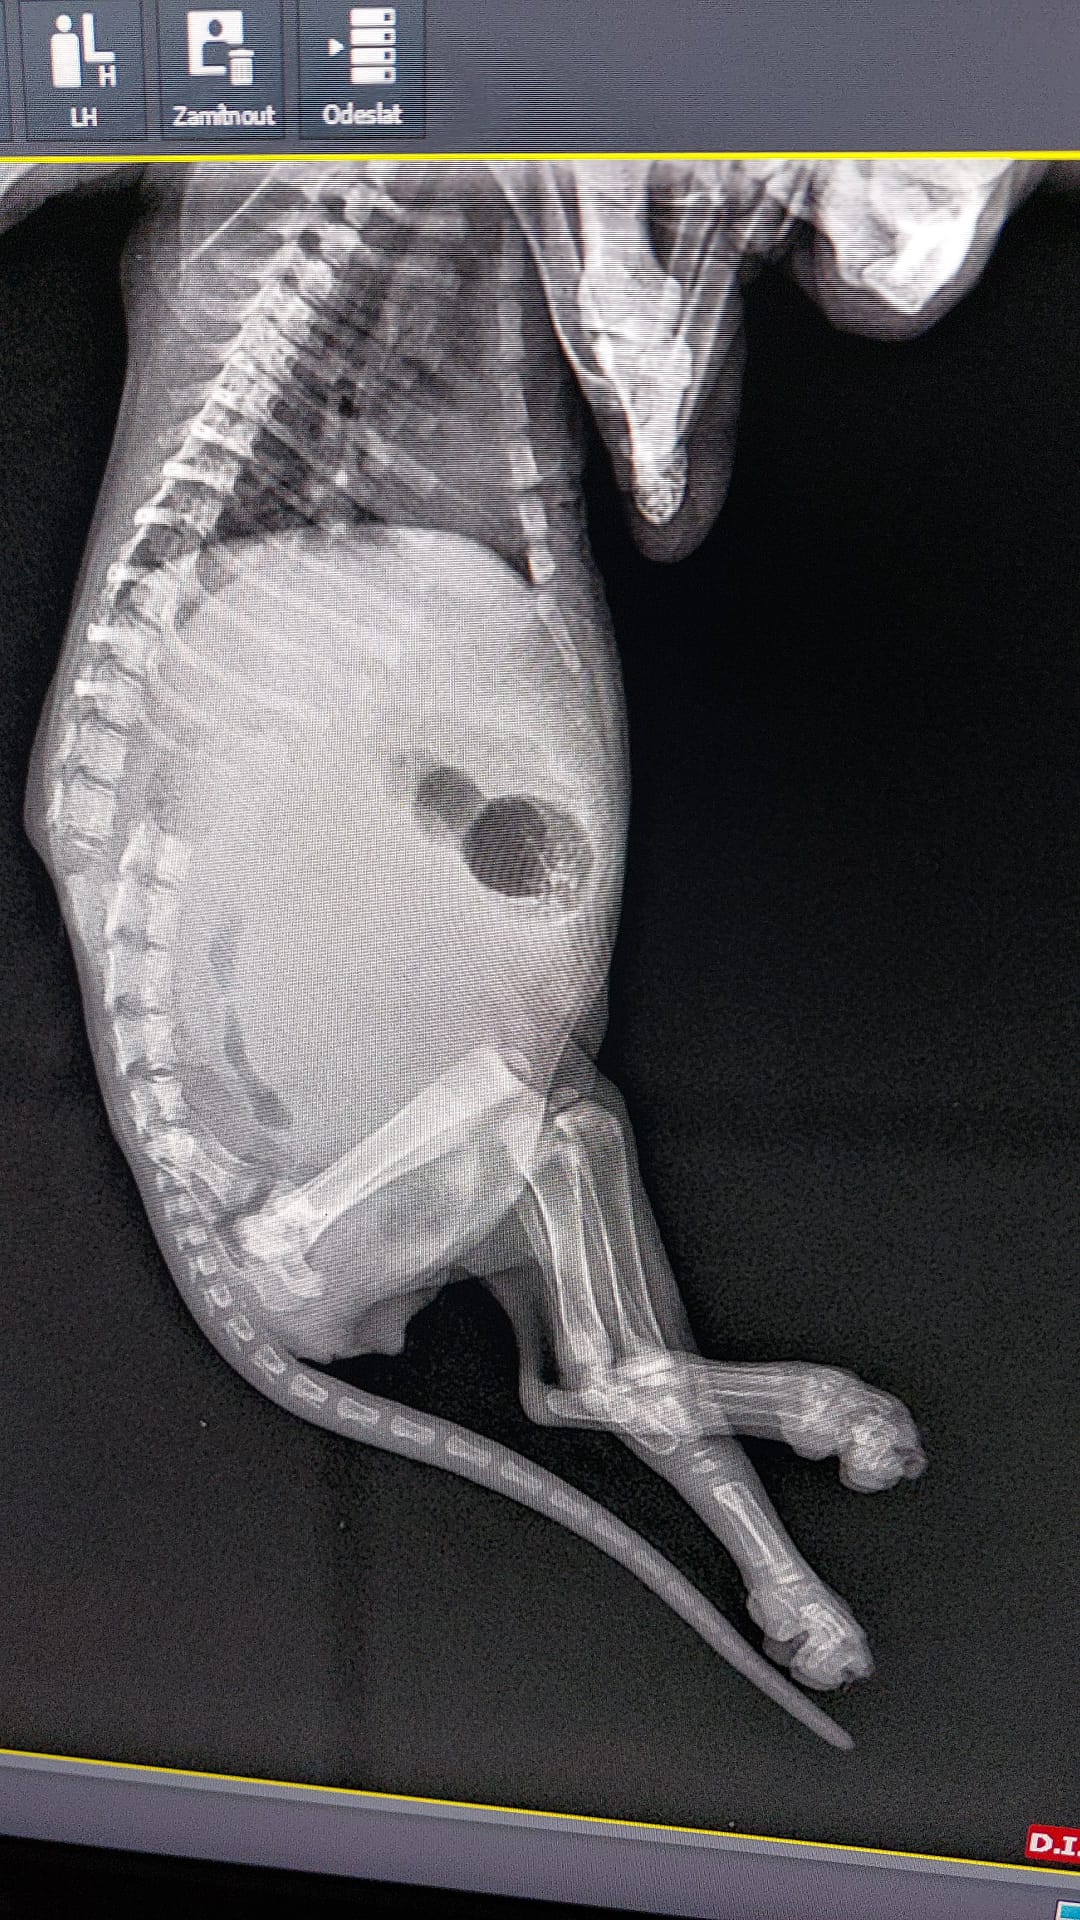

Paní mi přivezla v kýbli cca 2měsíční koťátko, které za sebou vleklo zadní nožky. Dle očekávání se ukázalo, že to bude navždy, jelikož koťátko má zlomenou páteř. Opět rozhodnutí - žít či nežít.

Musela jsem se naučit Mikeškovi pravidelně vymačkávat močový měchýř. Kocourek se sám neumí vyčůrat a bobkuje samovolně (to je ale nejmenší problém).